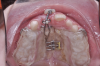

Fig 2. Initial situation of case involving an impacted maxillary right central incisor, frontal view (Fig 2) and occlusal view (Fig 3).

Fig 3. Initial situation of case involving an impacted maxillary right central incisor, frontal view (Fig 2) and occlusal view (Fig 3).